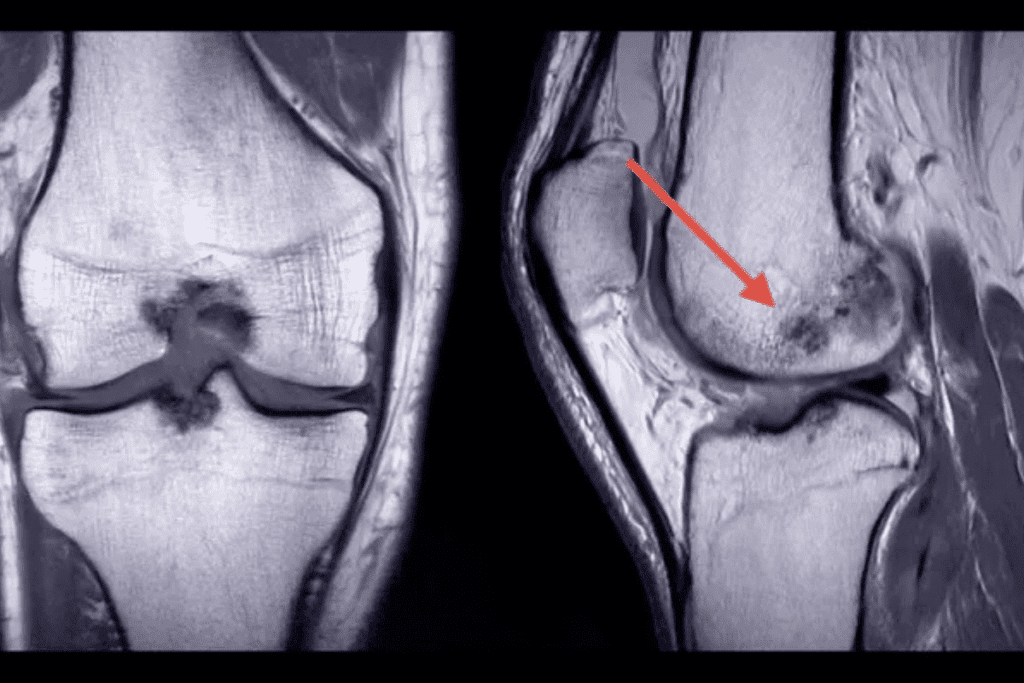

Clinical Case Examples

Clinical examples show MRI’s role in finding stress fractures. For example, a young athlete with leg pain and normal X-rays got an MRI. It found a stress fracture in the tibia. This led to quick treatment and prevented more harm.

These examples highlight MRI’s role in diagnosing stress fractures. It’s vital, even more so for high-risk individuals or when other tests are unclear.